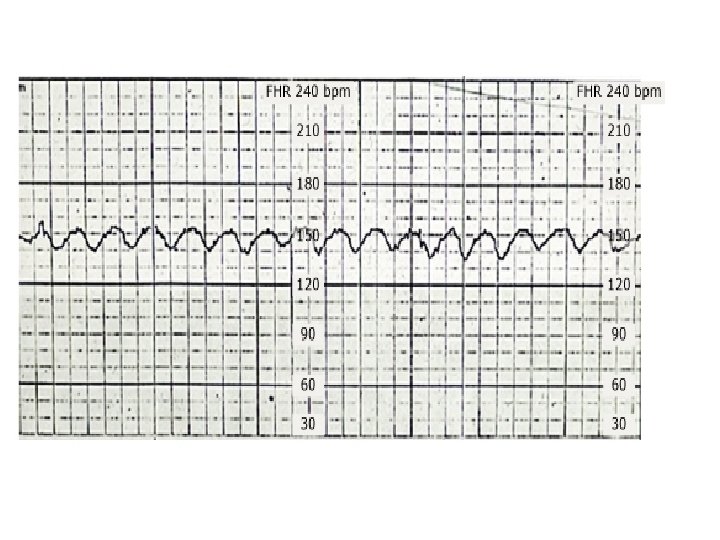

Sinusoidal and Pseudosinusoidal Patterns Sinusoidal pattern: A smooth, undulating pattern, lasting at least 10 minutes with a fixed period of three to five cycles per minute and an amplitude of 5 -15 bpm. Pseudosinusoidal: Usually caused by drugs such as Nubain or Stadol.

SALTATORY PATTERN 79